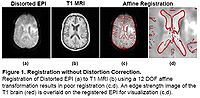

Registration without Correction

Localization of functional information relies on accurate registration of EPI and structural MR, which can be difficult due to EPI distortion caused by B0 field inhomogeneity. Correcting distortion using acquired Fieldmaps has been shown to improve registration [1], but Fieldmaps may not be available or may not be applicable if significant motion is present in the EPI, resulting in sub-optimal registration.